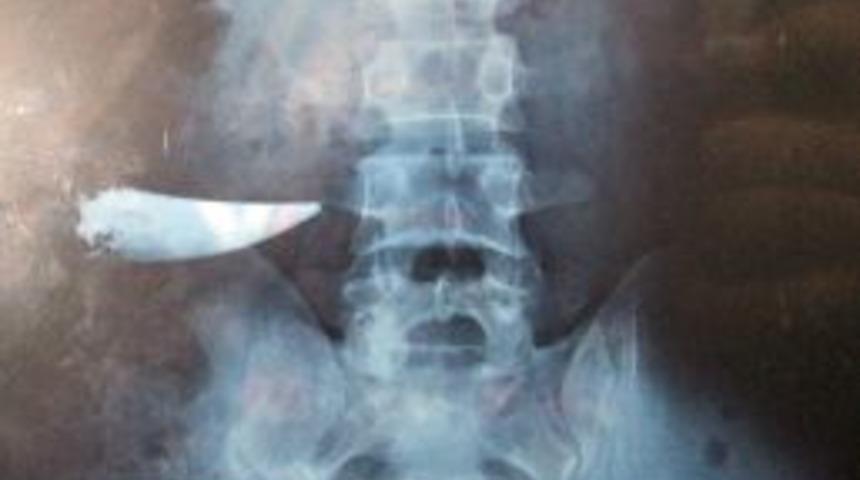

Edirne'nin Uzunköprü ilçesine bağlı Turnacı köyü doğumlu 9 yıl önce kavgada bıçaklanan, ameliyatın ardından taburcu edilen 37 yaşındaki Nihat Çevik'in karnında kavgada kullanılan bıçağın unutulduğu ortaya çıktı. Çevik'in karnındaki bıçakla 9 yıl yaşadığı belirlendi.

Nihat Çevik 2003 yılında bir köy düğünde çıkan tartışmada karnından bıçaklandı. Kan kaybı nedeniyle kendinden geçen Çevik, ambulansla Uzunköprü Devlet Hastanesi’ne kaldırıldı. Burada yapılan ameliyattan sonra odaya alınan Çevik 7 gün süren tedavinin altından taburcu edildi. Yarası tamamen iyileşen Uzunköprülü genç normal yaşamına döndü. Ardından çalışmak üzere İstanbul’a yerleşen Çevik, arkadaşına ait bir taşımacılık şirketinde masa başı işe başladı. Burada işine gidip gelen genç adam, zaman zaman büyük alışveriş merkezlerinin güvenlik kapısında geçişlerde sorun yaşadı. Çevik, büyük alışveriş merkezlerindeki güvenlik kapısından geçişler alarm sesi gelmesi üzerinde güvenlik görevlileri tarafından üzeri sıkı arandıktan sonra ancak içeri alınıyordu. Görevliler bu konuda zaman zaman tartışma yaşayan Çevik, 15 gün önce işyeri rampasından düştü. Bacağı incinen Çevik, İstanbul’daki özel bir hastaneye kaldırıldı. Çevik'in hastanede çekilen röntgeninde 9 yıl önce kavgada kullanılan bıçağın karnında unutulduğu belirlendi.

Çevik, evraklarını alarak Uzunköprü Devlet Hastanesi’ne geldi. Hastane bahçesinde açıklama yapan Nihat Çevik, 9 yıl önce bir düğünde yaşanan bıçaklanma olayından sonra kendinden geçmiş bir şekilde hastaneye getirildiğini söyledi. Hastanede ameliyat olduğunu anlatan Çevik, başka bir rahatsızlık için gittiği İstanbul’daki hastanede böyle bir durumun ortaya çıktığını belirtti.

Filmi gördükten sonra büyük bir şok yaşadığını ifade eden Çevik, içeride kırılan bıçağın çıkarılmayıp emaneten bir dikişin atıldığını iddia etti. Yaşadığı bu olaydan dolayı şikayetçi olduğunu kaydeden Çevik, bunun için avukatı aracılığıyla her türlü yasal hakkını arayacağını dile getirdi.